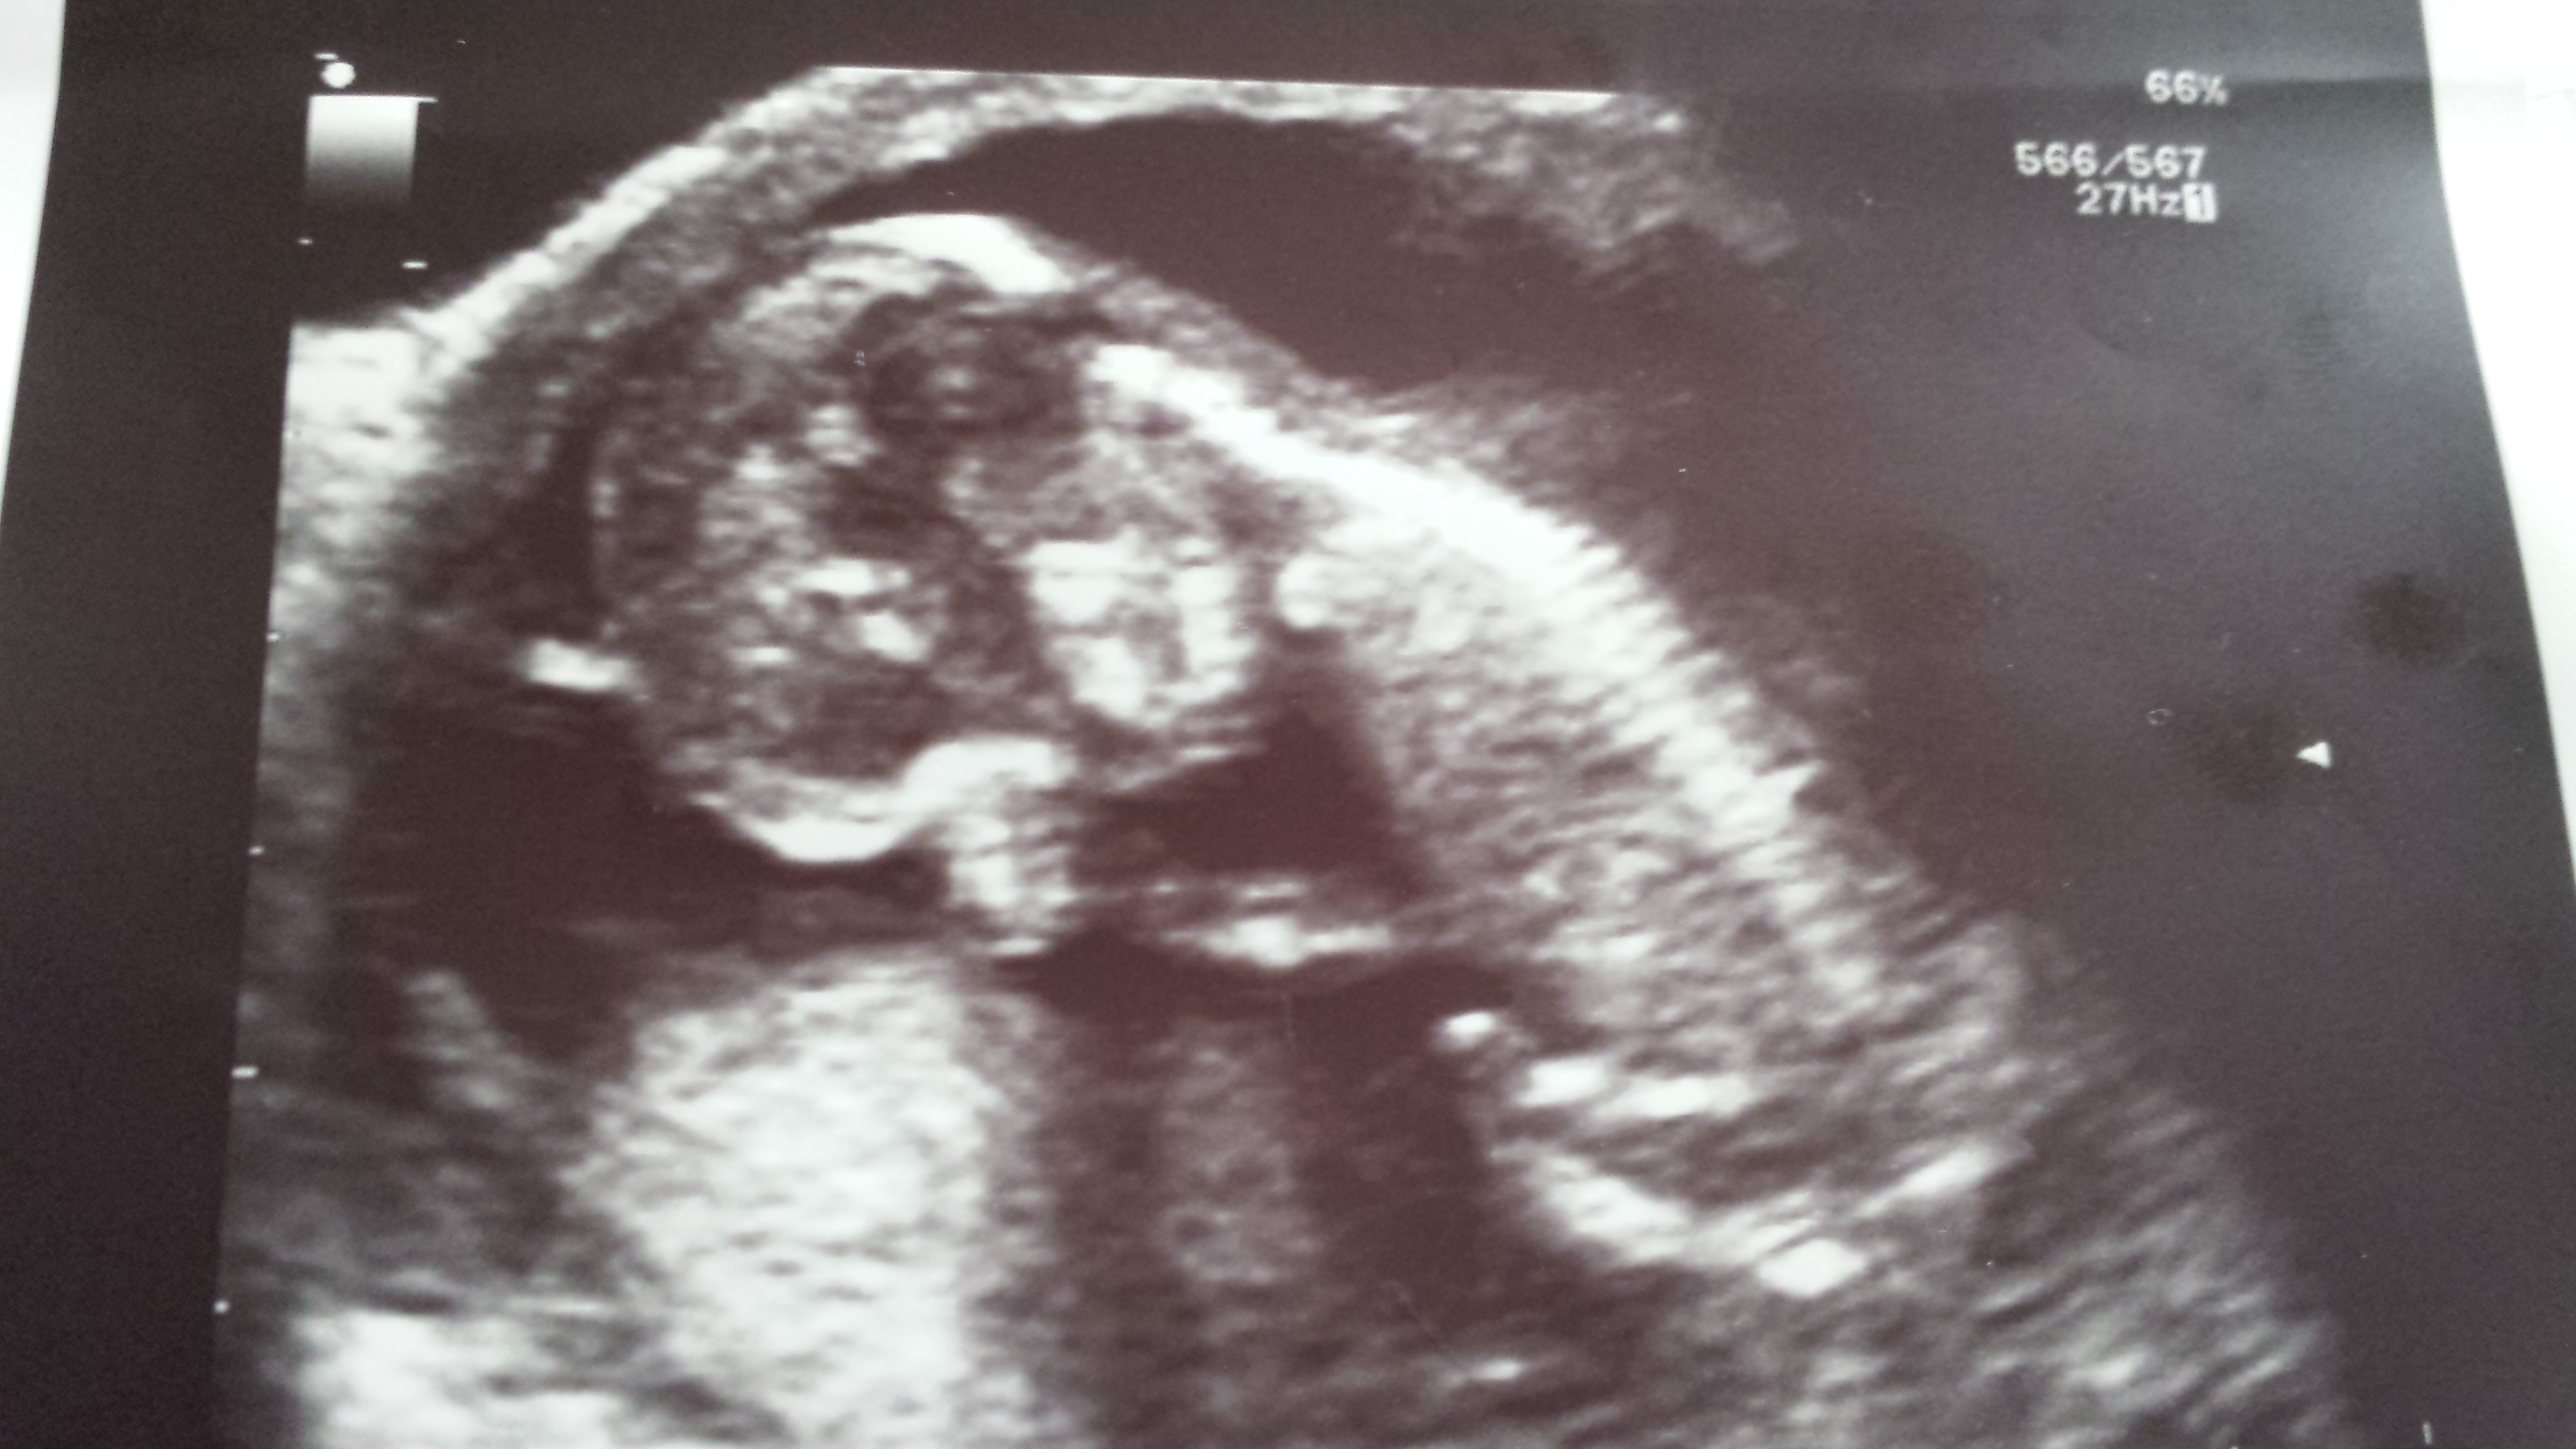

99% sure there is not one clue on gender between the 3 pics. Wanted to double check with you lovely ladies. Find out in just over 2 weeks. TIA.

I don't see any gender clues but get a boy vibe.

From my understanding of skull theory i'd say boy.

The baby is back out so no gender clues but from skull I'd say boy

So we had our gender scan yesterday at 16+2 and we were confidently told we are having a girl. I can't be so sure though. The potty shot has no 3 lines and a 4d image shows what I think are boy parts.

Yep thats a girl. On a 4d at 16 weeks you will still sort of see a protrusion as its not quite done sinking all the way back yet.